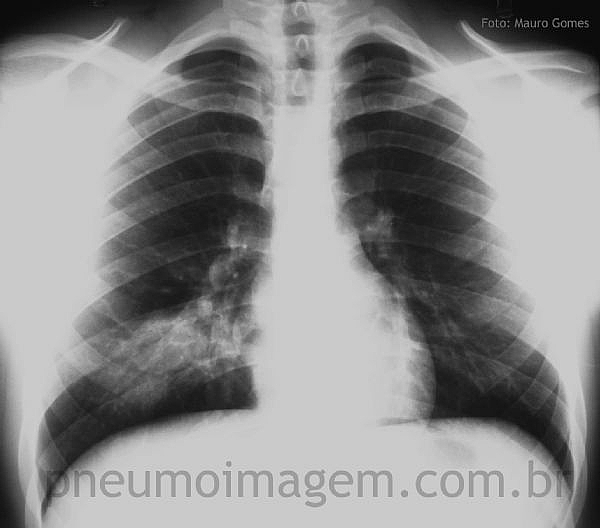

DESTAQUES DO CHEST 2015: MAIORES RISCOS EM PNEUMONIA ADQUIRIDA NA COMUNIDADE

Dr. Marcos Restrepo apresentou que a DPOC está associada a maior risco de pneumonia adquirida na comunidade (PAC) e a diferenciação entre exacerbação da doença e PAC muitas vezes é difícil. No entanto, ainda não foi demonstrado que portadores de DPOC com PAC possuem pior prognóstico comparados aos demais sem DPOC. Idosos com DPOC e doença cardíaca prévia possuem maior mortalidade em pneumonia.

Dr. Carlos Luna afirmou que DPOC e doença cardíaca são as principais doenças associadas em PAC. Pacientes com pneumonia possuem maior risco de eventos cardiovasculares, tais como arritmia, falência cardíaca e doença coronariana aguda, e isso aumenta o risco de morte em 30 dias.